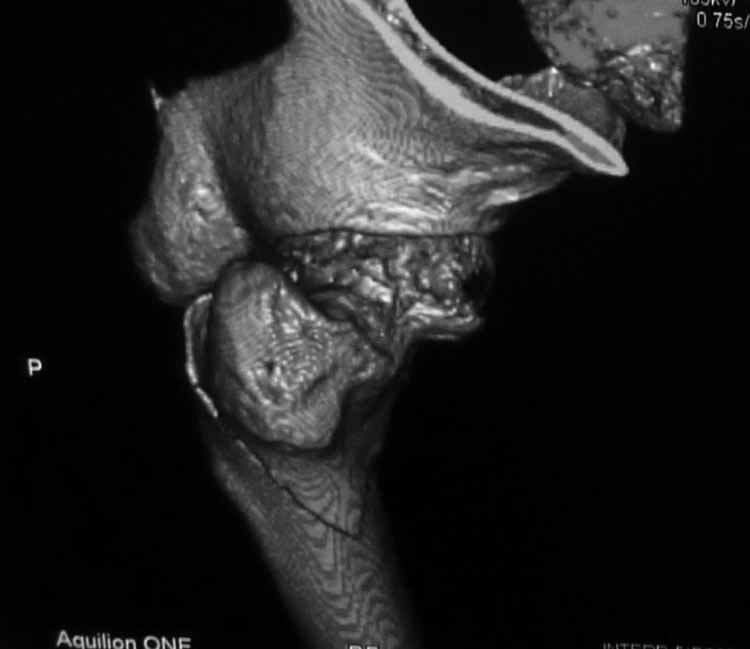

Пациентка 53 лет. ДТП 09.01.12: сочетанная травма: перелом 2-5 ребер справа, ушиб легких;

перелом обеих лонных костей без смещения; закрытый перелом проксимального конца правой

бедренной кости; открытый оскольчатый внутрисуставной перелом проксимальных концов

костей правой голени.

Бедро одномоментно делать не стал, не было уверенности в наличии перелома на уровне шейки. Во время операции смотрел тазобедренный сустав под ЭОПом,

головка неподвижна. После операции повторили КТ, стало очевидно, что имеется субкапитальный перелом. Что делать, остесинтез или протезирование? Если остеосинтез, то чем? Заранее благодарен за советы.